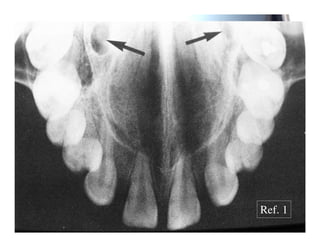

2 4 (

; 0 0- 4 ( 0 89 0! "" : F :8